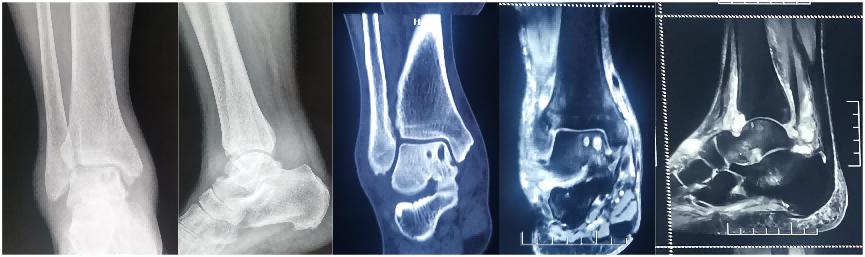

经过全面系统的专业检查,最终诊断为右踝滑膜炎、距骨囊肿、距骨软骨损伤。孙启彬认为可以行踝关节镜微创手术解决,患者欣然同意手术方案。

在孙启彬主任医师带领下,运动医学科团队为其成功实施了踝关节镜下前后联合入路全滑膜切除、距骨骨囊肿刮除、自体髂骨骨软骨移植。手术非常成功,术后患者几乎没有明显的肿胀疼痛,恢复良好,术后3天满意出院。